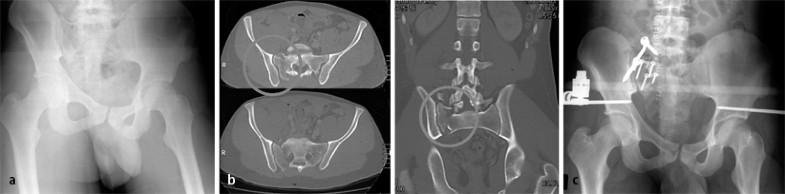

Die für die Stabilität des Beckenrings relevanten Strukturen liegen dorsal (Fall 3, Abb. 3). Wird ein aufnahmetechnisch unzureichendes und somit nicht aussagefähiges Bild als solches akzeptiert, ohne dass die Entscheidung zur weiterführenden Bildgebung (CT) bei entsprechender Anamnese und Klinik fällt, können Verletzungen der Iliosakralgelenke und des Sakrums (zumeist B-, aber auch C-Verletzungen) übersehen werden (Fall 3, Abb. 3). Dies bedeutet nicht, dass „vorsichtshalber“ zum Ausschluss einer Schädigung der posterioren Beckenringstrukturen grundsätzlich ein CT angefertigt werden sollte, da dies beim jungen Patienten zur hohen Strahlenbelastung der Gonaden, bei der rasch zunehmenden Zahl älterer und geriatrischer Patienten zu einer Überdiagnostik ohne therapeutische Konsequenz führt. Gerade bei Letzteren ist es ratsam, im Zweifelsfall einen Mobilisationsversuch zu unternehmen und bei persistierenden Beschwerden unter ausreichender Schmerzmedikation und mangelndem Mobilisationsforschritt ein CT in der 2. Woche nach dem Trauma durchzuführen [13].

Fall 3, 24-Jähriger mit isolierter Beckenringverletzung AO 62C1.3, a unzureichende a.-p. Aufnahme des Beckens, b CT mit koronarer Rekonstruktion: C-Verletzung mit vertikalem Versatz, Abriss des Querfortsatzes von LWK5 rechts, mehrfragmentärer Stauchungsfraktur des Sakrums, c offene Reposition, weitere Erläuterungen s. Kasuistik

Fall 3

Bei dem 24 Jahre alten männlichen Patienten war es bei einem Motorradunfall zu einer isolierten Beckenringverletzung (AO 62C1.3) gekommen. Die a.-p. Aufnahme des Beckens (Abb. 3 a) war lagerungs- und aufnahmetechnisch unzureichend. Die CT-Aufnahmen mit koronarer Rekonstruktion belegten eine C-Verletzung mit vertikalem Versatz sowie Abriss des Querfortsatzes von LWK5 rechts und eine mehrfragmentärer Stauchungsfraktur des Sakrums (Abb. 3 b).

Die Versorgung erfolgte durch offene Reposition der Sakrumfraktur mit winkelstabiler Platte und spinopelviner Transfixation bzw. supraazetabulärem Fixateur externe.